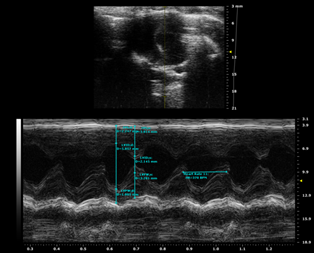

圖注:TAC模型心電圖

圖注:TAC模型4周后心電圖